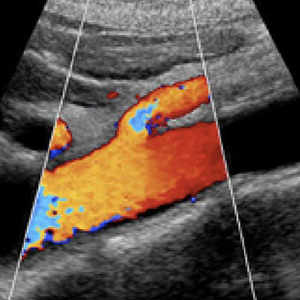

This exam evaluates your two main vessels, the Inferior Vena Cava (IVC) and aorta. A dilated IVC can be an indication of right heart failure. 1 in 6 males over 60 years old have an abdominal aorta aneurysm and the survival rate is 50% if the aneurysm ruptures.